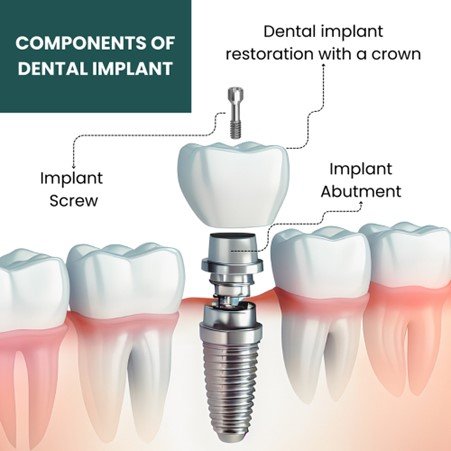

5. Final Placement of the Crown

Approximately two weeks after impressions are taken, your custom-made crown will be ready for placement. This final step ensures your implant is both functional and aesthetically pleasing, blending seamlessly with your natural teeth.